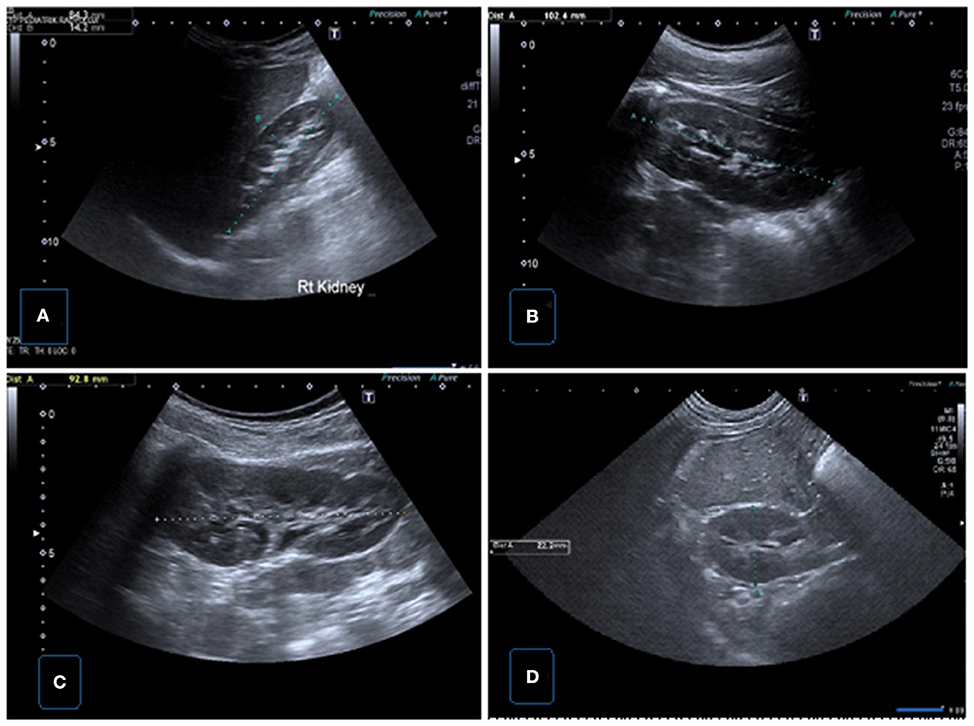

ccr31934-toc-0001-m.jpg?trick=。Frontiers | Urinary Ultrasound and Other Imaging for。Ultrasound of the Urinary System | SpringerLink。【書籍の概要】本書は腎臓超音波検査に特化した図版集であり、医療従事者や学生にとって貴重な参考資料です。視覚的な情報が豊富で、腎臓の解剖や病理を理解するのに役立ちます。【内容の特徴】各章には腎臓に関する詳細な超音波画像とともに、解説が付されています。これにより、実際の診断や研究に役立つ情報が得られます。【対象読者】医療従事者、特に放射線技師や腎臓専門医、または腎臓に関心のある学生に最適です。- 書名: ATLAS OF Renal Ultrasonography- 著者: O'NEILL- 内容: 腎臓超音波検査に関する図版と解説- 表紙の色: 青と赤のグラデーションご覧いただきありがとうございます。。。【 新品未使用 】 最新医学大辞典。宇宙論と神。DVD>松本岐子先生 明日からの臨床に使える鍼灸療法 1巻2巻set。専用⭐︎美品】健康管理士一般指導員 検定書セット 1-6巻。未開封品 DVD 岩橋 亮平 4回リピート制! 産後ママに評判の骨盤矯正